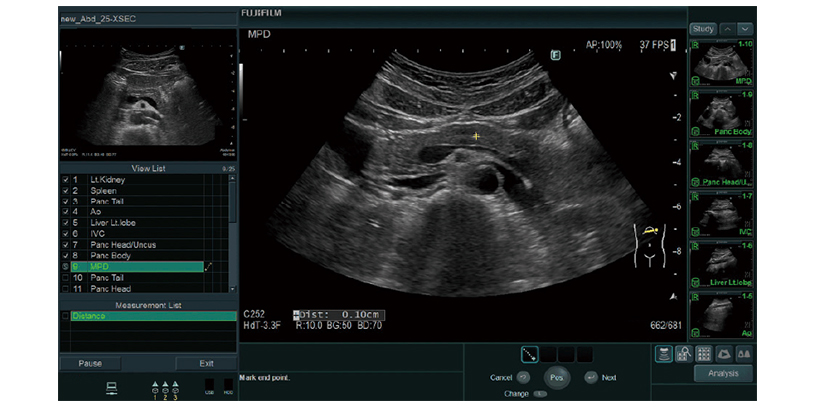

Prior fixed examination protocols and imaging conditions can be registered. Button operations can be reduced significantly to support efficient examinations. Additionally, a reference image can be displayed via the "Guide View" function.